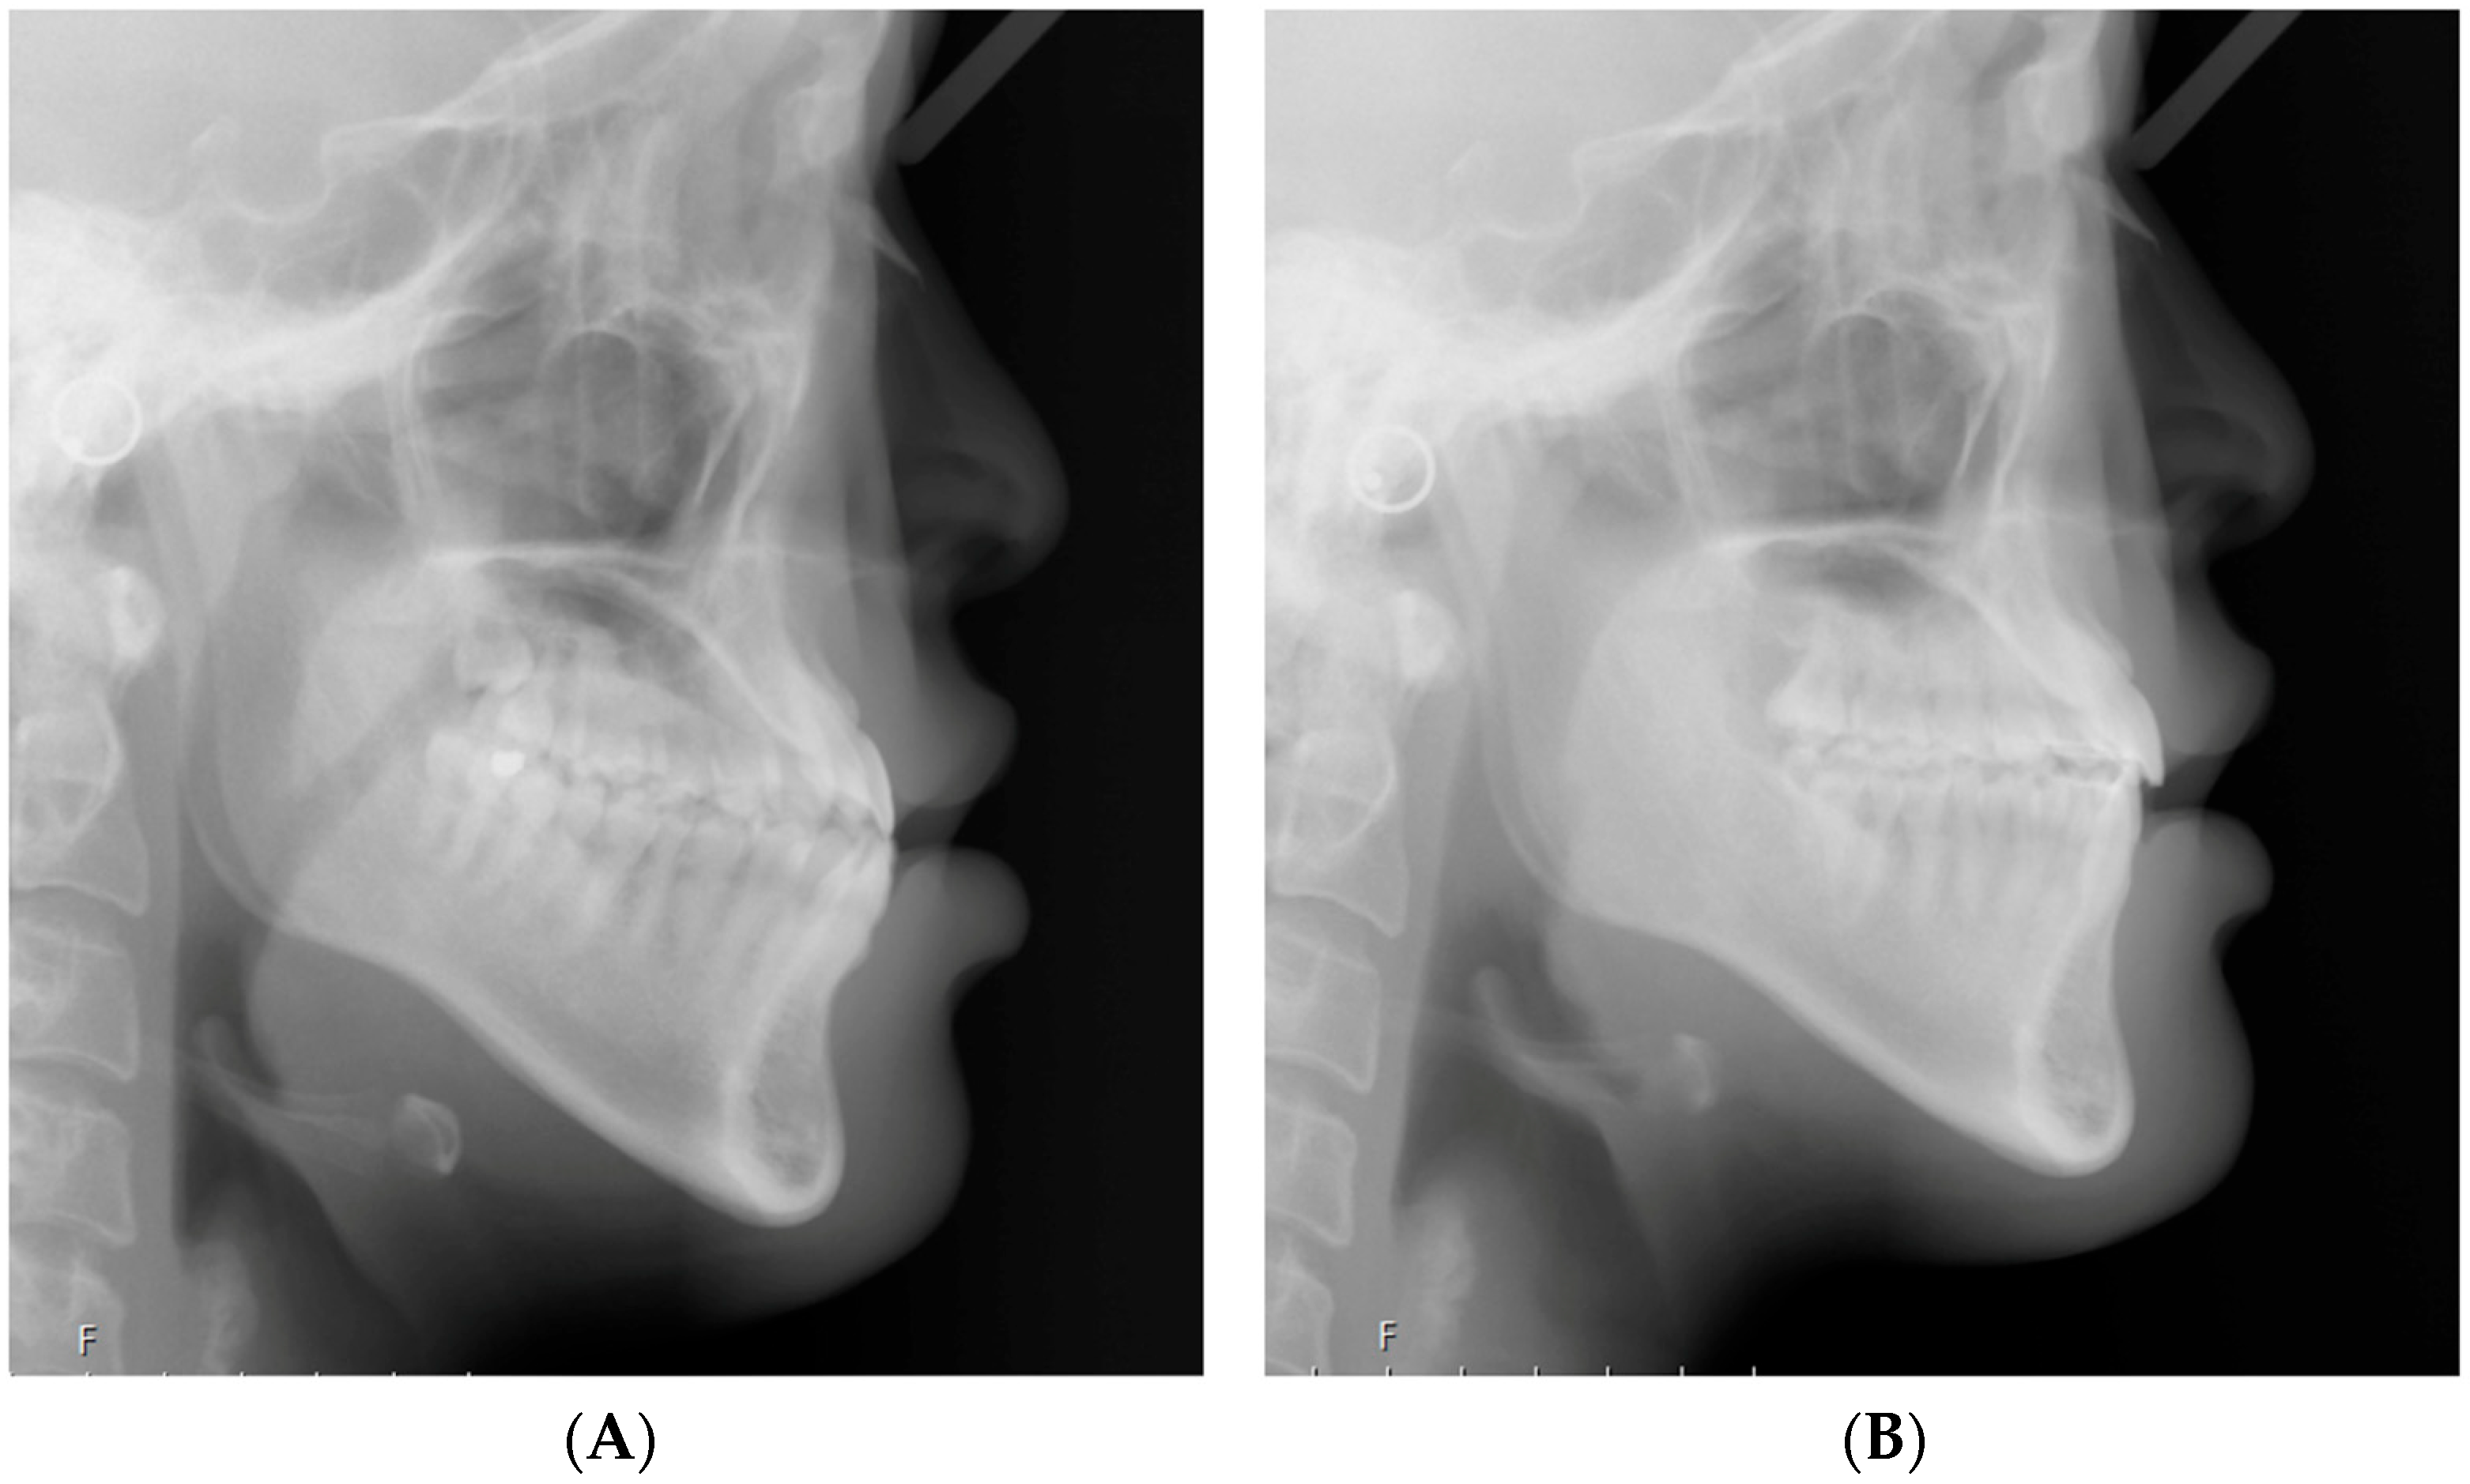

2.2. Cephalometric Analysis

| SNA (°) | 82.14 ± 3.70 | 81.99 ± 3.73 | −0.15 | 0.419 |

| SNB (°) | 83.21 ± 3.73 | 82.84 ± 3.54 | −0.37 | 0.114 † |

| ANB (°) | −1.07 ± 2.30 | −0.66 ± 2.26 | 0.41 | 0.123 |

| Wits appraisal (mm) | −7.06 ± 1.89 | −5.50 ± 2.29 | 1.56 | 0.000 * |

| Pog to N perpendicular (mm) | 4.43 ± 5.71 | 4.40 ± 5.59 | −0.03 | 0.946 |

| FMA (°) | 26.86 ± 6.79 | 27.03 ± 6.78 | 0.17 | 0.550 |

| Facial height ratio (%) | 65.46 ± 5.12 | 65.68 ± 4.88 | 0.22 | 0.496 |